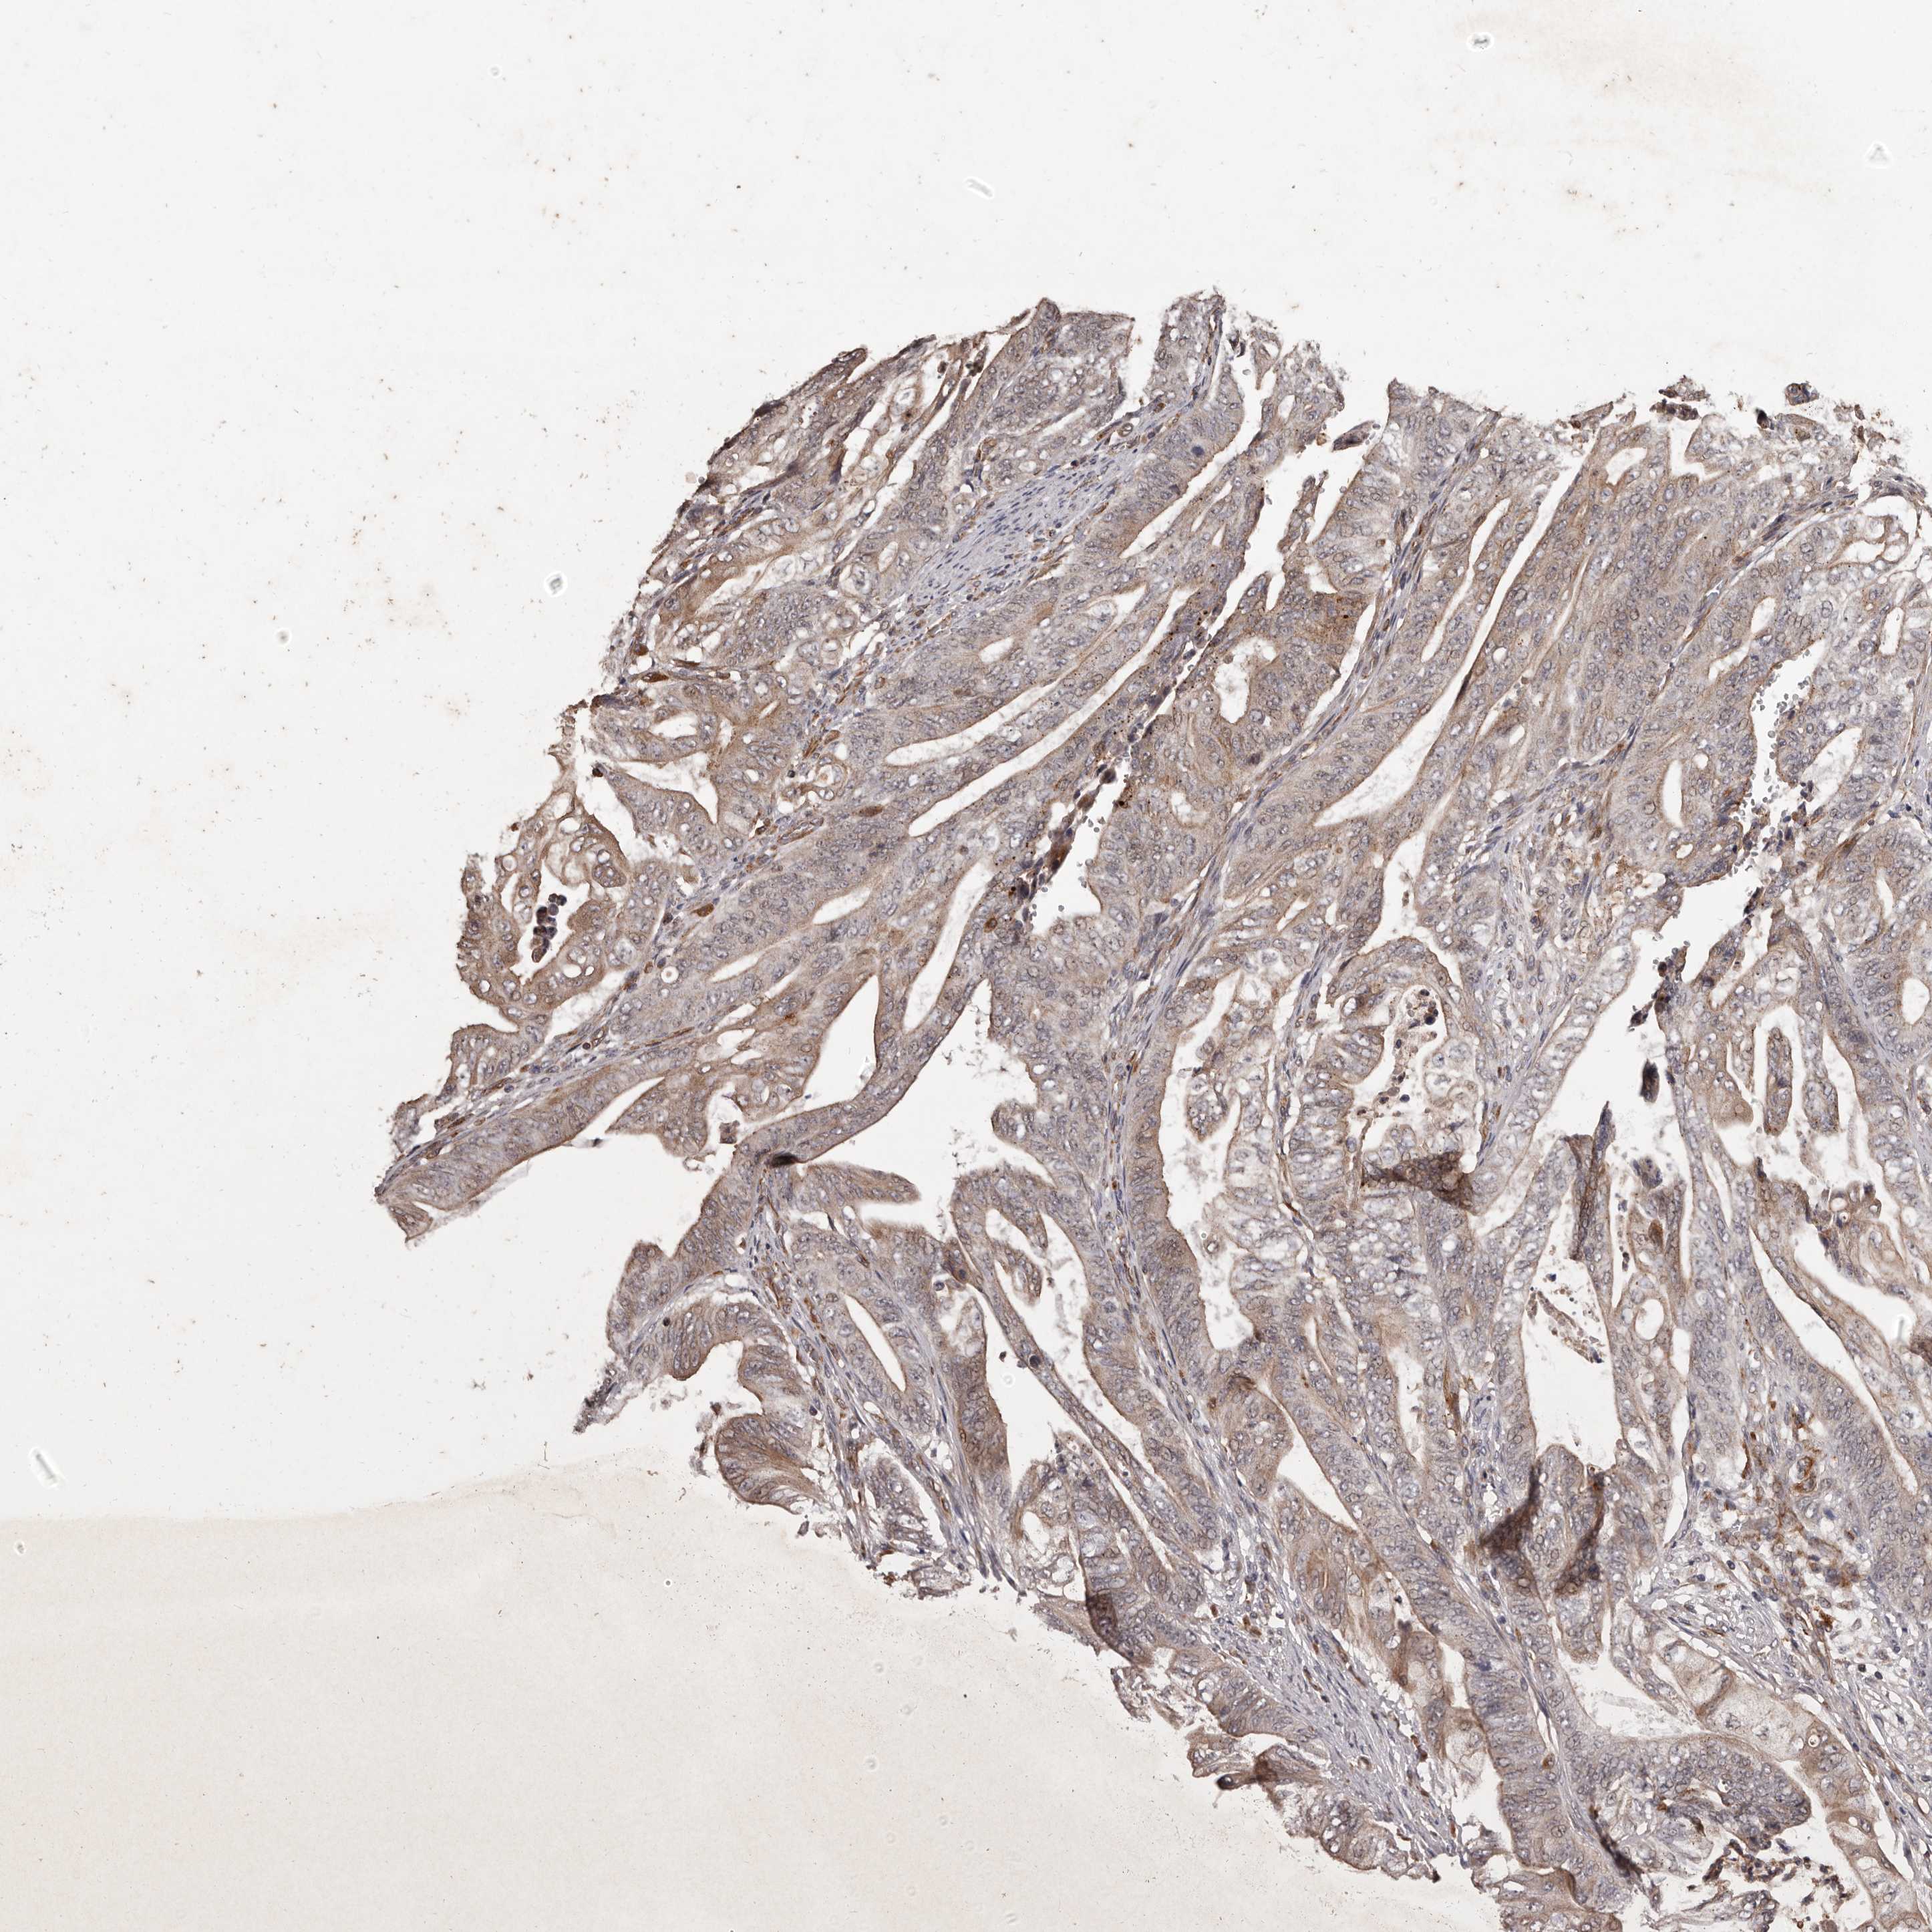

STOMACH CANCER - Protein expressioni

A mouse-over function shows sample information and annotation data. Click on an image to view it in a full screen mode. Samples can be filtered based on level of antibody staining by selecting one or several of the following categories: high, medium, low and not detected. The assay and annotation is described here.

Note that samples used for immunohistochemistry by the Human Protein Atlas do not correspond to samples in the TCGA dataset.

Antibody stainingi

Antibody staining in the annotated cell types in the current human tissue is reported as not detected, low, medium, or high, based on conventional immunohistochemistry profiling in selected tissues. This score is based on the combination of the staining intensity and fraction of stained cells.

Each image is clickable and will lead to virtual microscopy that enables deeper exploration of all samples and also displays staining intensity scores, fraction scores and subcellular localization as well as patient and tissue information for each sample.

Antibody HPA029455

Staining

High

Medium

Low

Not detected

Intensity

Strong

Moderate

Weak

Negative

Quantity

>75%

75%-25%

<25%

None

Location

Nuclear

Cytoplasmic/membranous

Cytoplasmic/membranous,nuclear

Adenocarcinoma, NOS